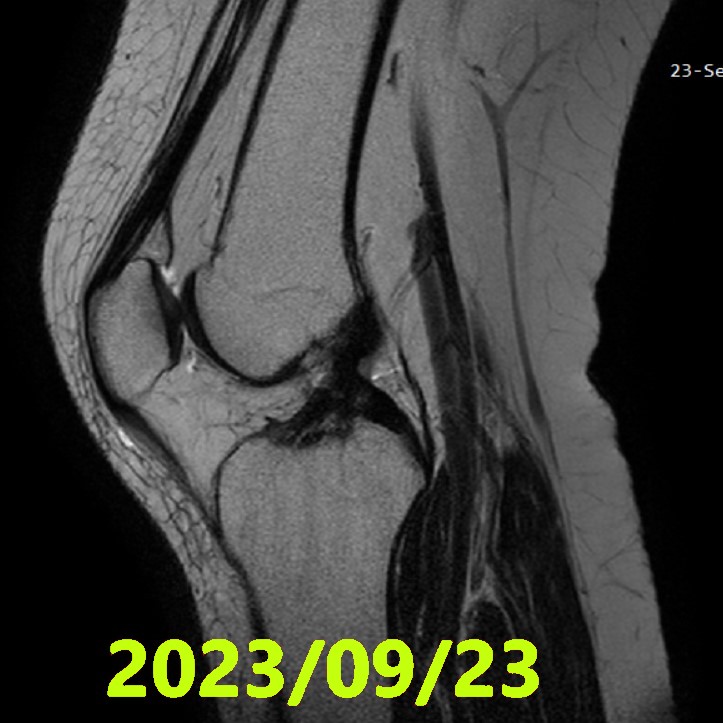

最終評估(MRI ②)

- 拍攝日期:2023 年 9 月 23 日(治療開始約 4.5 個月後)

- 評估:經 3 名獨立影像專家合議判定

- ACLOAS 判定:最終判定為 1 型(Grade 1:良好的形態與連續性保存)

- 復歸情況:已完全回歸日常生活,膝關節穩定度表現優異。